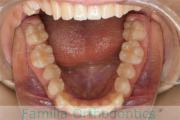

歯並びを治したいということで来院されました。下あごがやや右側に偏位して後退している、上顎前突(出っ歯)でした。上下左右から小臼歯を抜歯して、歯科矯正用アンカースクリューを併用したマルチブラケット法にて治療を行いました。約2年、24回の来院をしていただきました。

下顎の後退はいびきなどの上部気道の障害が出やすいと考えられます。